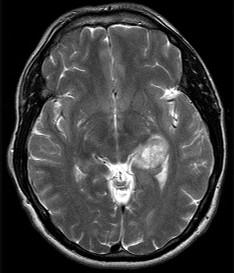

问题 下列哪项符合胶质母细胞瘤(如图所示)的特点()

选项 A.主要发生于儿童 B.以额叶最多见 C.位于大脑半球灰质内 D.血运不丰富 E.周围水肿不明显

答案 B